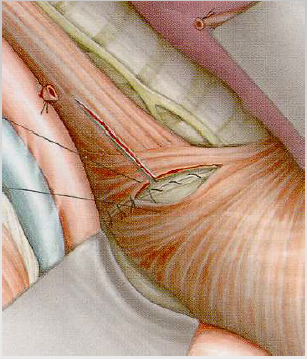

Miotomiya

Kiçik (<2 sm) divertikullarda göstərişdir. Krikofarengeal əzələ boylama istiqamətdə 3 sm kəsilir.

Divertikulektomiya və miotomiya

Ən radikal müalicə üsuludur. Divertikul boyun nahiyəsindən kəsilir, atılır və miotomiya edilir. 90% hallarda nəticə qənaətbəxş olur.

Endoskopik stapler

Divertikul ilə QB arasındakı arakəsmə endoskopik staplerlə kəsilir və tikilir. 3-6 sm ölçülü divertikullarda icra edilir.

Cərrahi müalicə - 3-komponentli cərrahi müalicə (laparoskopik yol daha çox tövsiyə edilir):

- Divertikulektomiya

- Miotomiya – divertikulun əks tərəfindən aparılır. Kəsik divertikulun boyunu səviyyəsindən başlanılır və mədəyə doğru 2 sm uzadılır.

- Hissəvi fundoplikasiya reflüksü önləmək üçün icra edilir.